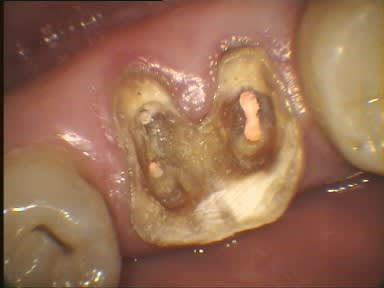

J'ai déjà récupéré de nombreuses racines à ce stade et les ai utilisées comme piliers de bridges ou les ai couronnées, dans la mesure ou l'ancrage alvéolaire était solide et en respectant les furcations pour y assurer l'hygiène.

La gencive lasérisée devient très ferme avec le temps et le déchaussement se stabilise. Ces restaurations se comportent bien sur un recul de plusieurs années.

Un exemple: une 46 avec furcation linguale dénudée après lasérisation et restauration par une endocouronne céromère réalisée il y a 9 ans et sans signe clinique avec une excellente attache gingivale malgré la perte osseuse, les 3 avant dernières images ont été prises lors d'un contrôle en mars dernier ...

9 années pour cette patiente de 90 ans, cela vaut bien le coup d'essayer vous ne croyez-pas? (dernière radio)

Avec le laser, on devient bien plus conservateur...